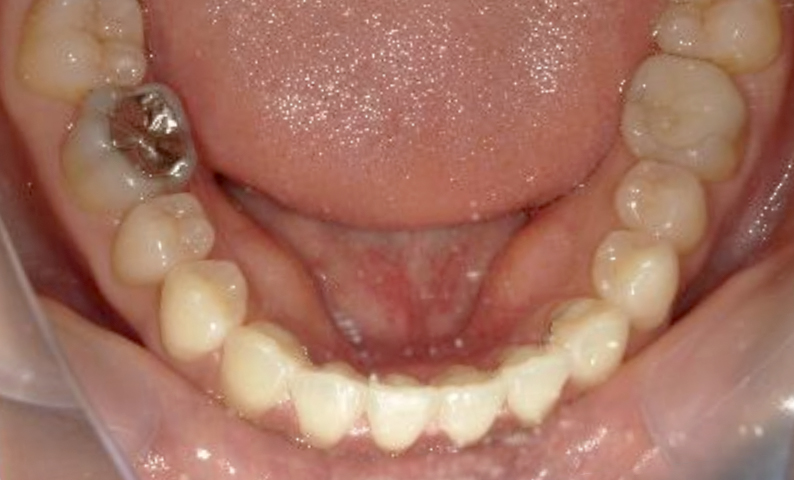

| 治療前 | 治療後 |

|---|---|

|